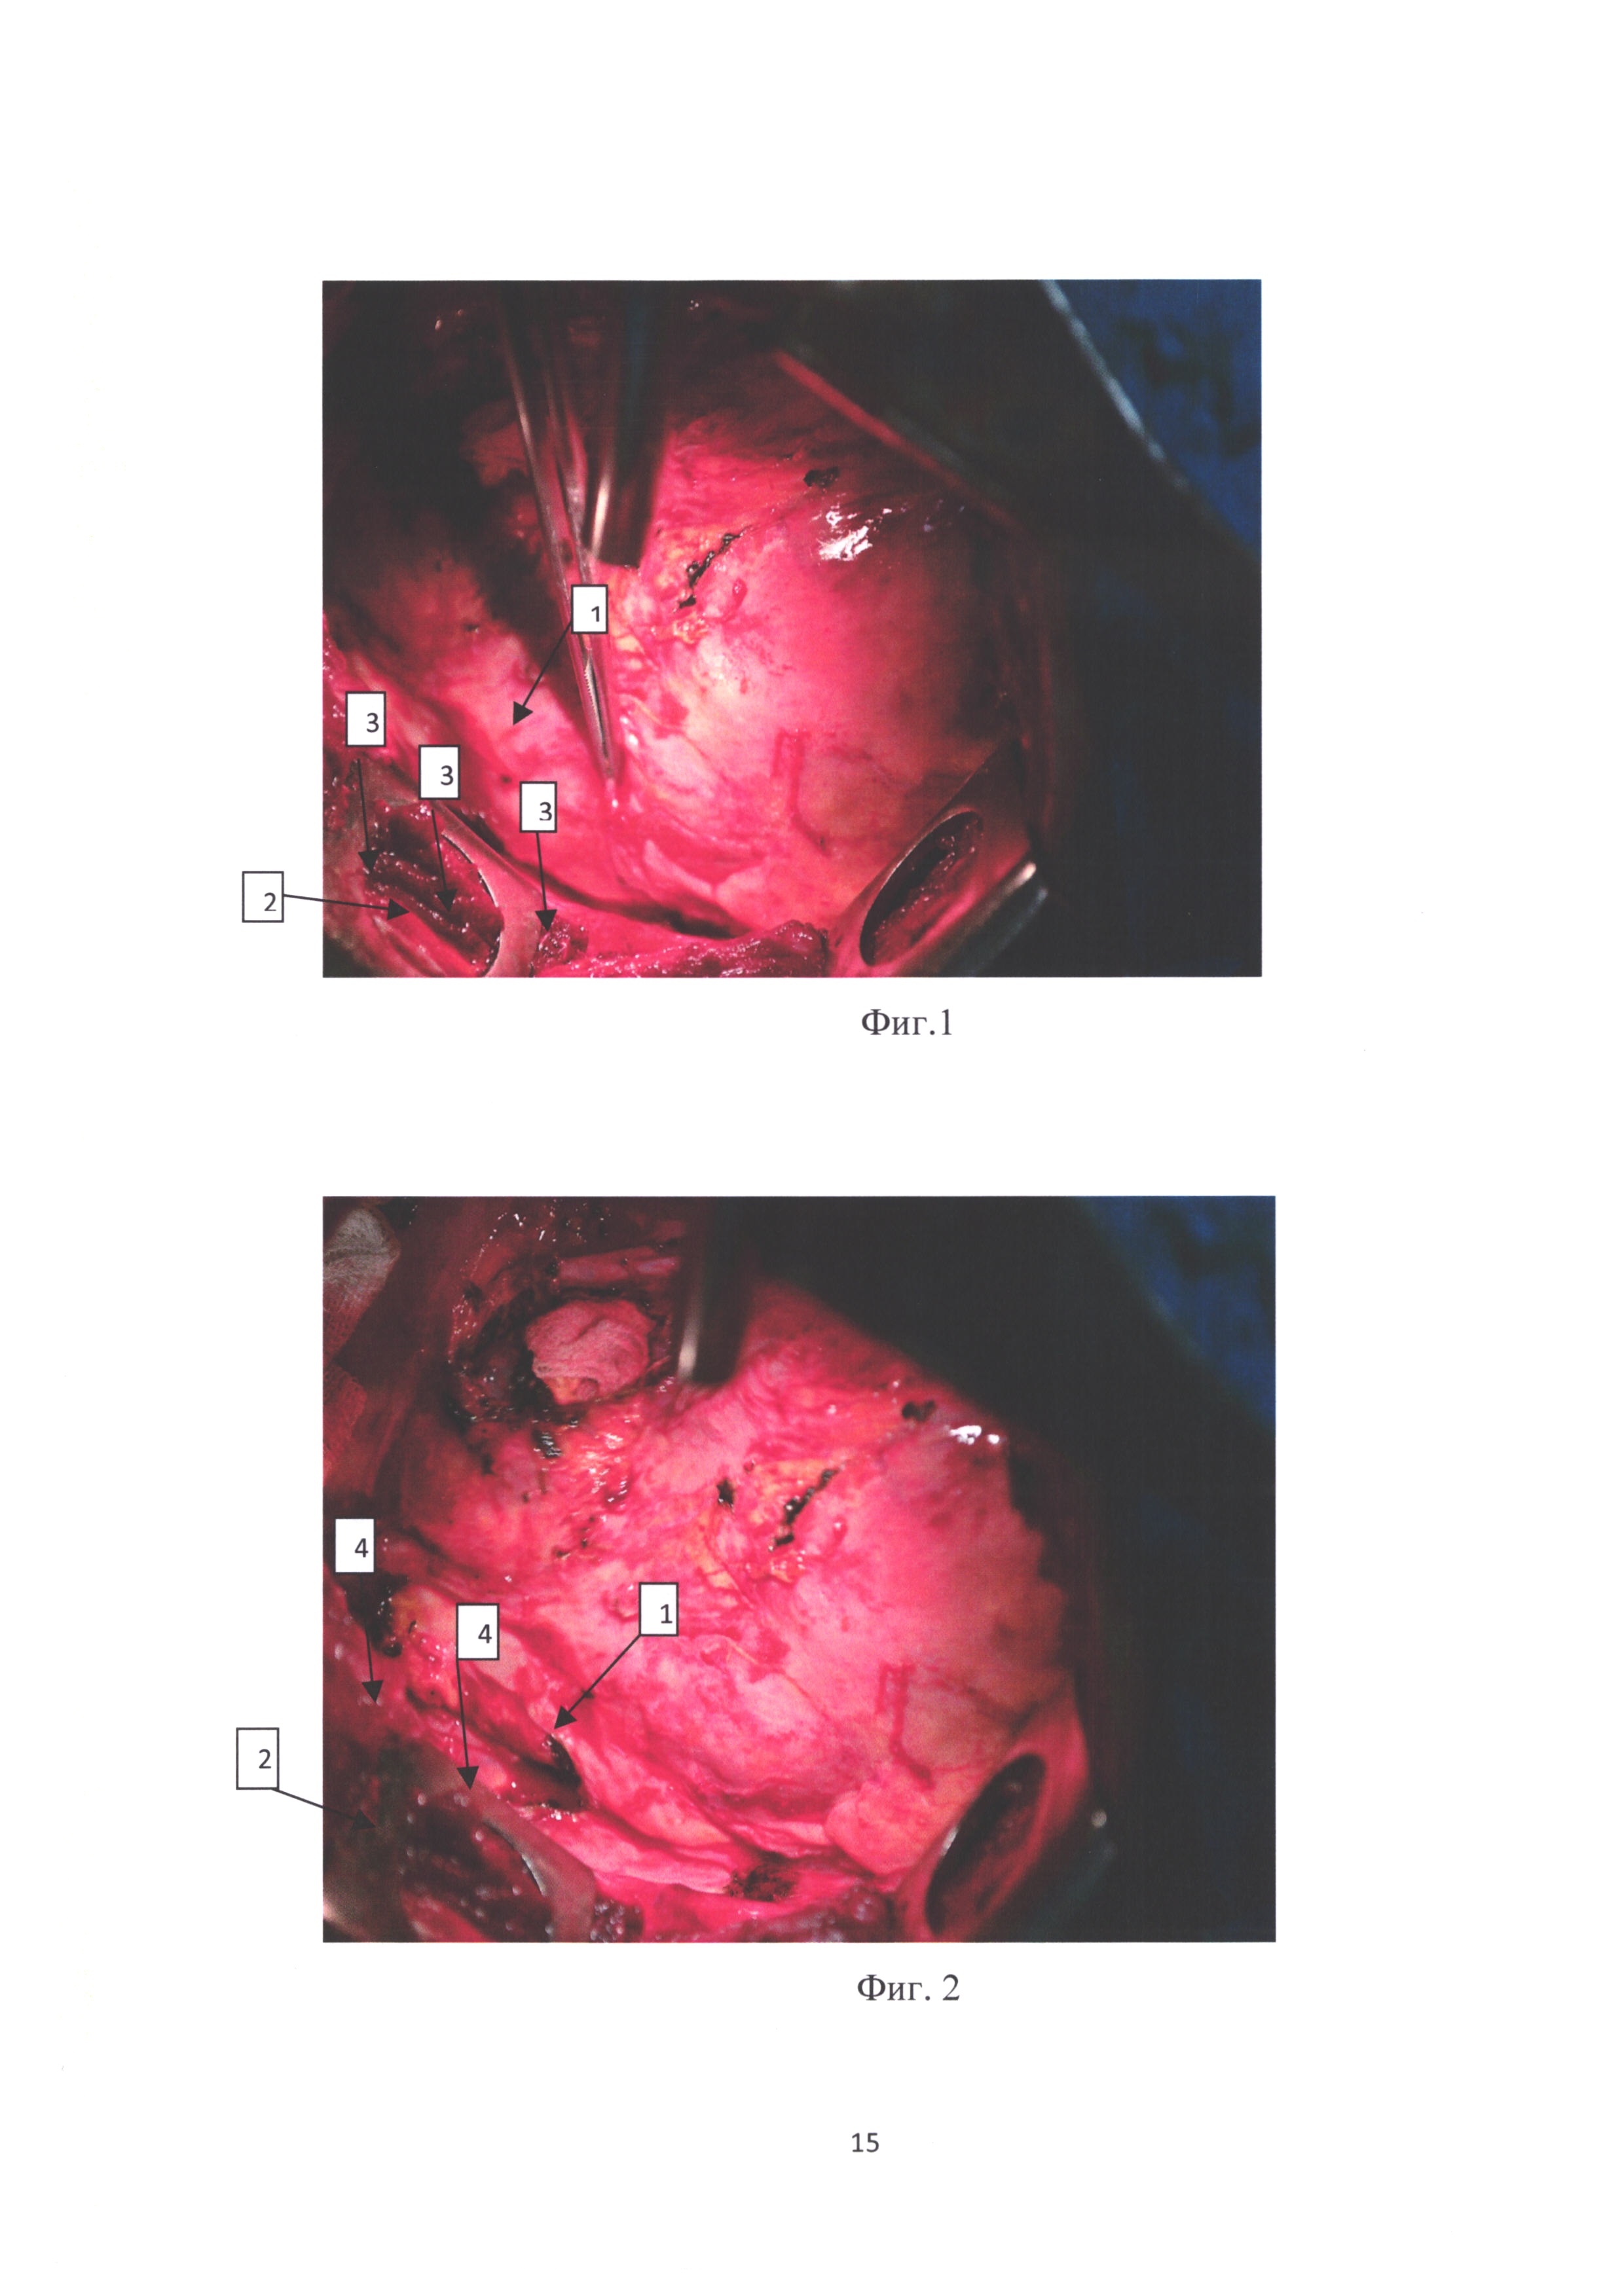

фиг. 2 - переднее средостение после удаления легкого, где виден грыжевой мешок;

[32]

фиг. 3 - переднее средостение после медиастинопластики.

На чертежах обозначены:

[34]

1 - перикард, 2 - передняя грудная стенка, 3 - грыжевые ворота, 4 - грыжевой мешок, 5 - швы после медиастинопластики.

Выполняются последовательно следующие операции, которые иллюстрируются фото, представленными на фиг. 1-3.

[37]